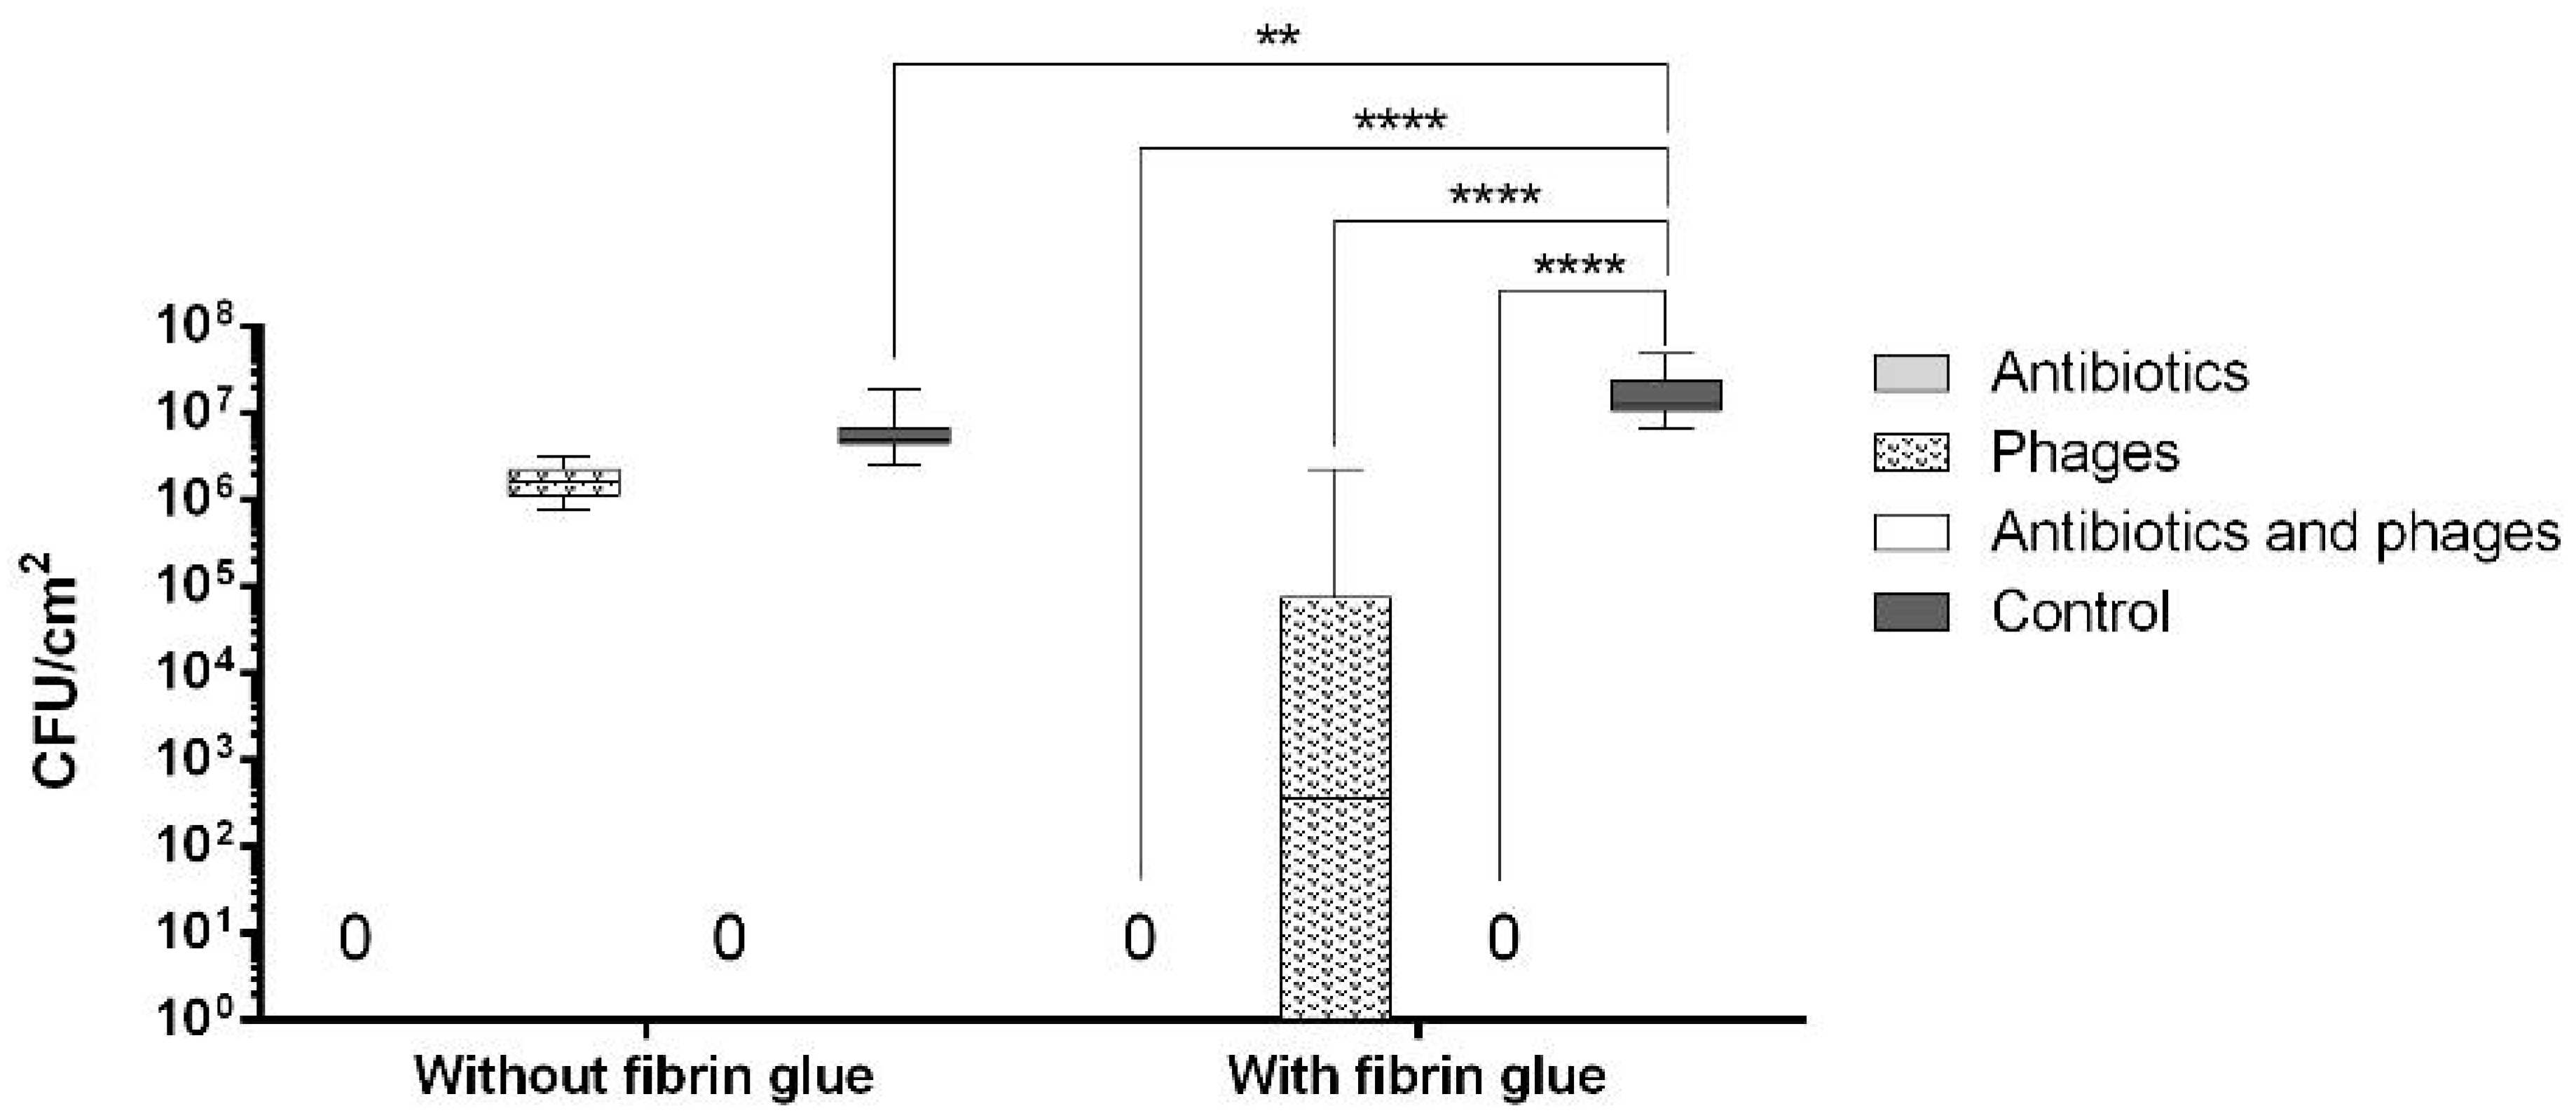

2.2. Antibacterial Loads of Graft Samples

2.2.1. Uncoated Grafts

2.2.2. Coated Grafts

2.3. Antibacterial Activity against Single Contamination

2.3.1. Activity against Staphylococcus aureus

2.3.2. Activity against Escherichia coli

2.4. Antibacterial Activity against Recurrent Contamination